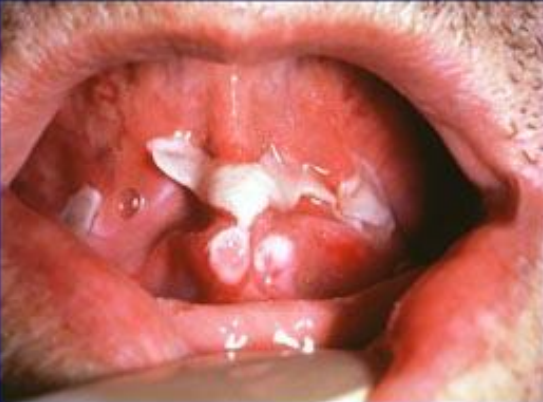

A 50 year old male complains of red, crusted painful lesions in the mouth and weight loss. How do you arrive at a differential for this guy?

Weight loss points you in the direction of an autoimmune disorder. The lesions in the mouth point you towards pemphigus vulgaris.

What are your major concerns with a patient who has widespread pemphigus vulgaris?

Fluid loss and superinfection

What histologic marker indicates autoantibody against desmoglein?

Acantholysis and rounded epithelial cells

What type of hypersensitivity causes this condition?

Type II. IgG tags desmogleins in the epidermis.